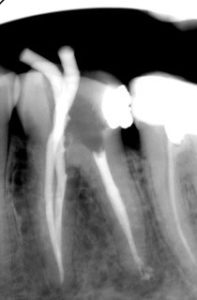

W naszym gabinecie w Gdańsku postawiliśmy na najwyższą precyzję, dlatego większość zabiegów endodontycznych

wykonujemy pod mikroskopem stomatologicznym.

Cały proces jest starannie kontrolowany radiologicznie. Wybierając Prodent Gdańsk, wybierasz leczenie na światowym

poziomie.